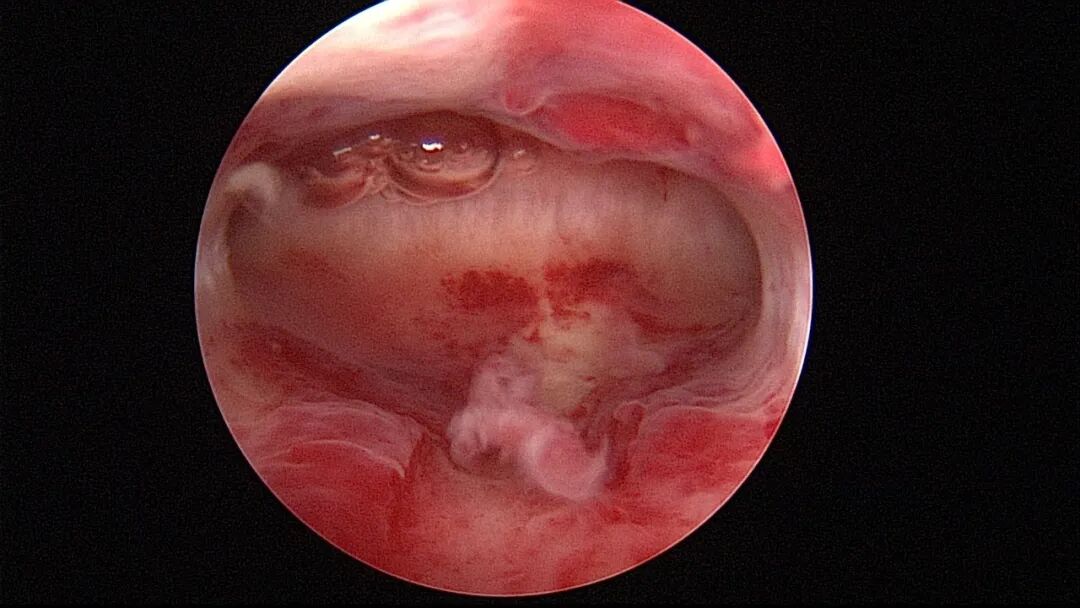

第一次宫腔镜:2021年4月,闭经50+天,B超提示宫腔粘连,宫腔镜探查见宫颈管上段封闭粘连,宫腔广泛粘连,AFS评12分(最高分)。宫腔镜单极电切分粘,恢复宫腔形态,显露双侧输卵管开口,右侧宫角附近内膜柔软、红润,宫腔防粘连复发处理。